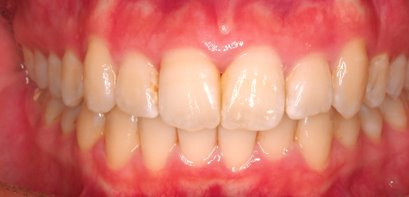

治療前

治療終了前